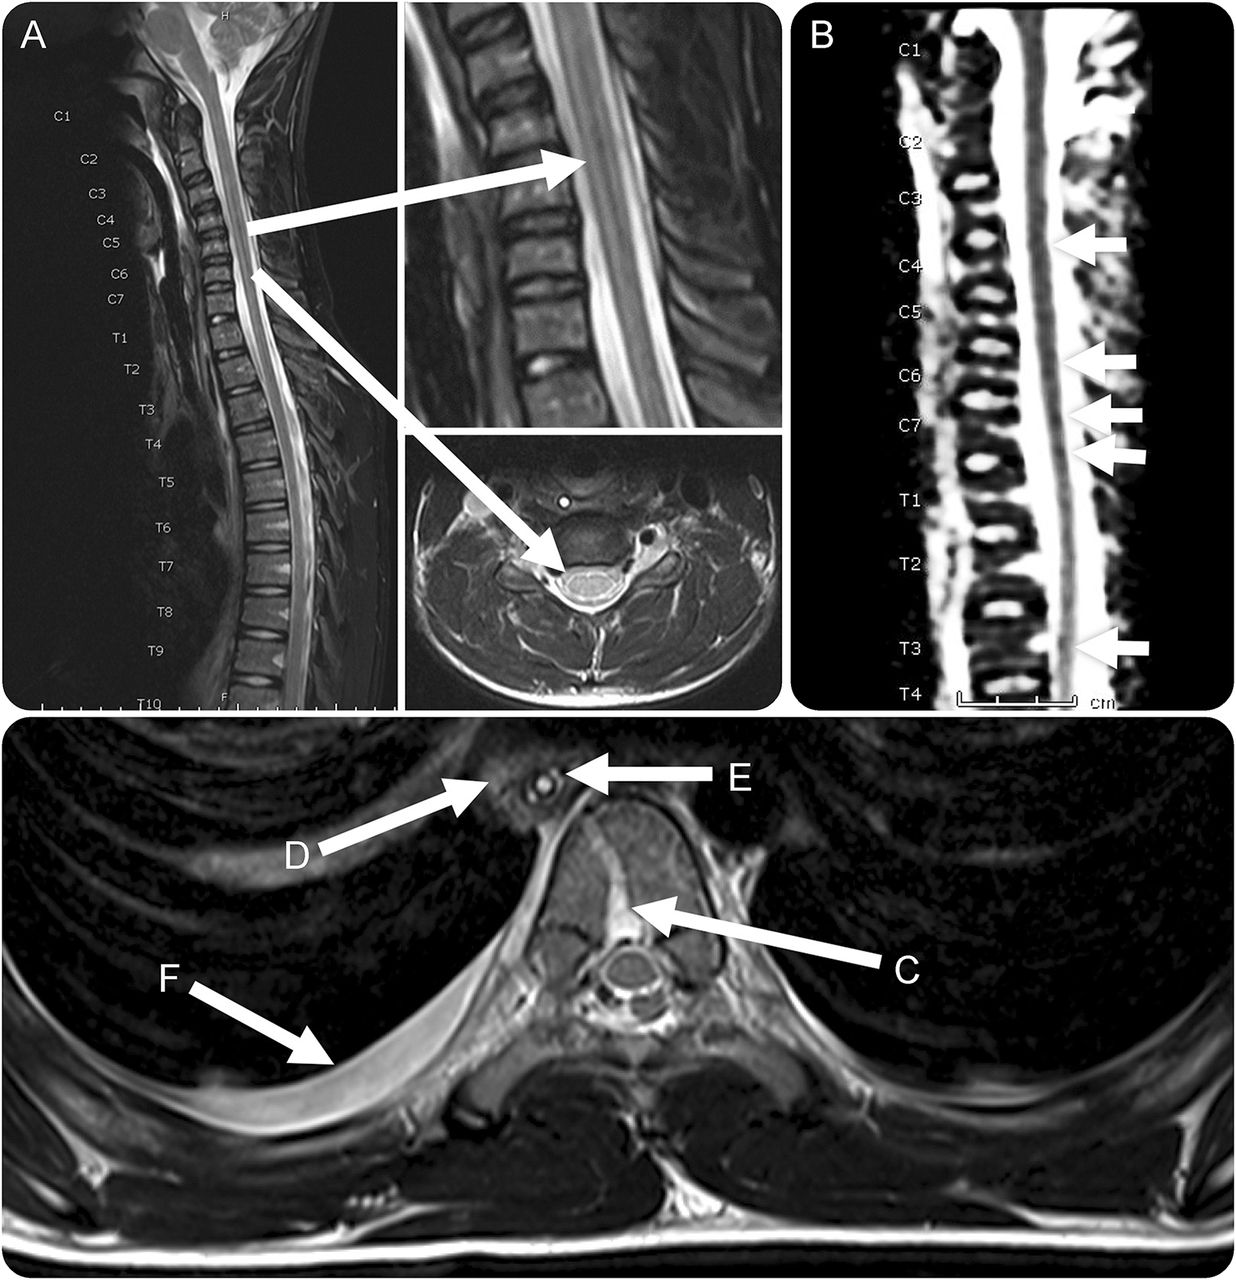

MRI T2和表观扩散系数序列颈和上胸脊柱

微妙的证据T2 hyperintensity整个脊髓(A) (B)表观扩散系数变化二次静脉充血的基部的脊椎神经丛(C)纵隔炎有关。(D)可以通过增厚墙食管(E) intra-luminal原位胃管,peri-oesophageal炎症和胸膜腔积液(F)。